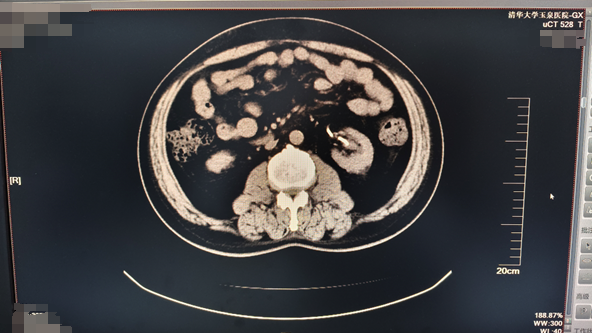

患者,男,61岁,主因“发现左肾鹿角形结石1月余”入院。泌尿系CT显示:左肾鹿角状结石;右肾结石。后在可控负压吸引下行输尿管软镜钬激光碎石术治疗肾结石。

前示图如下:

术后效果

术后6周复查泌尿系CT,左输尿管内支架置入术后,左肾结石基本消失。